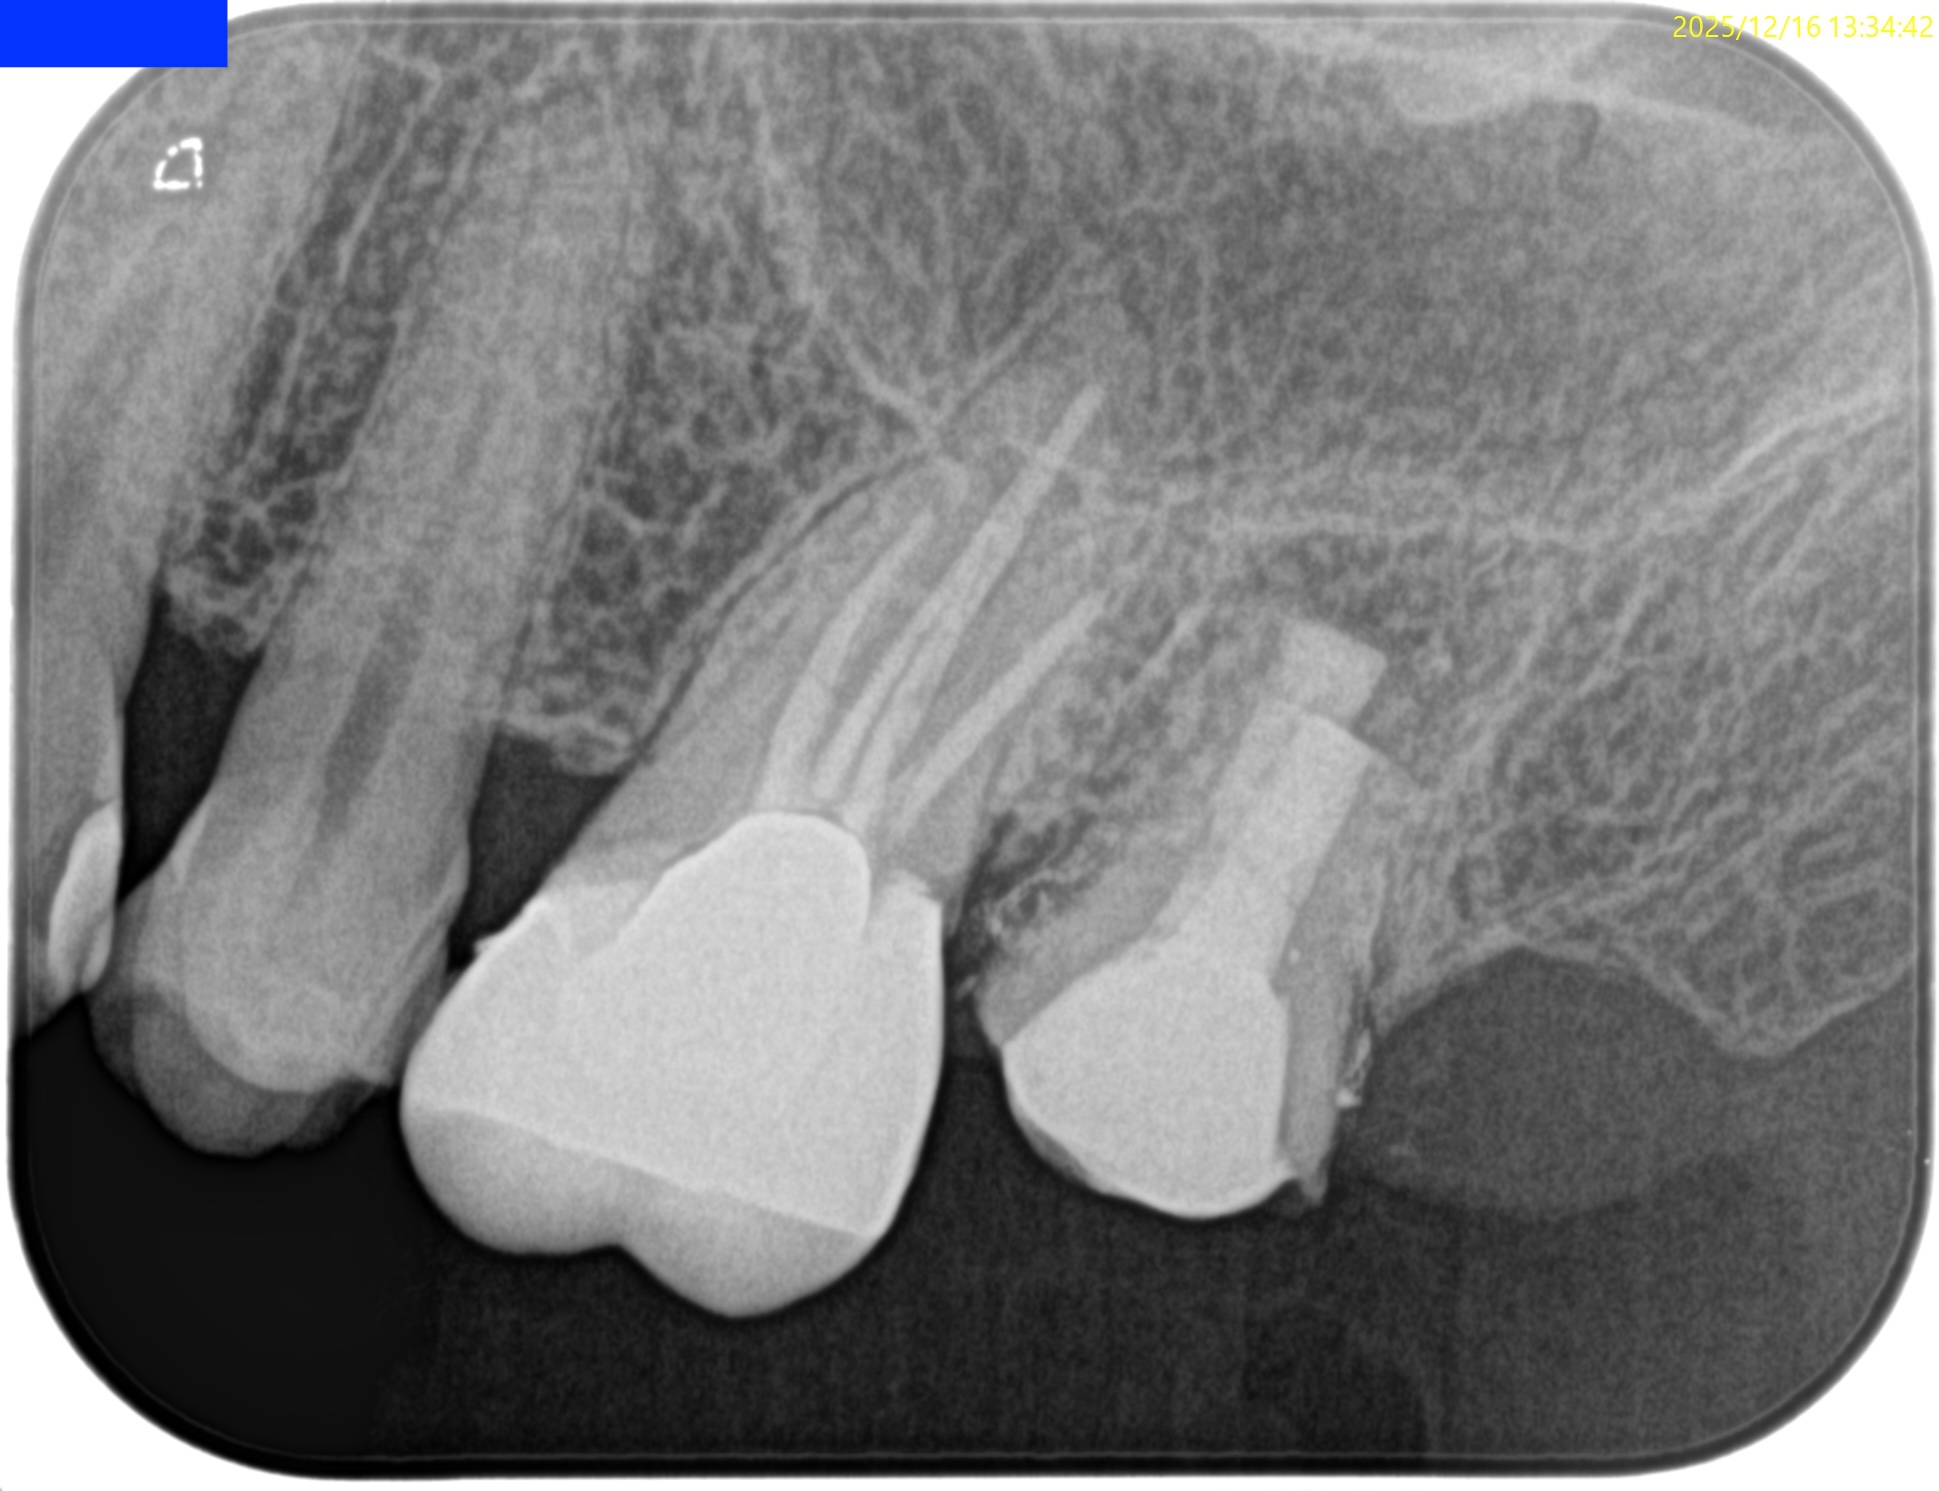

2年前から治療しても良くならないのは、

①ラバーダムを使用しない根管治療

②すでに非外科的歯内療法が適応しないくらい根尖部がすでに拡大されてしまっている

ことに起因する。

術後にPAを撮影した。

問題はないだろう。

術後にPA, CBCTを撮影した。